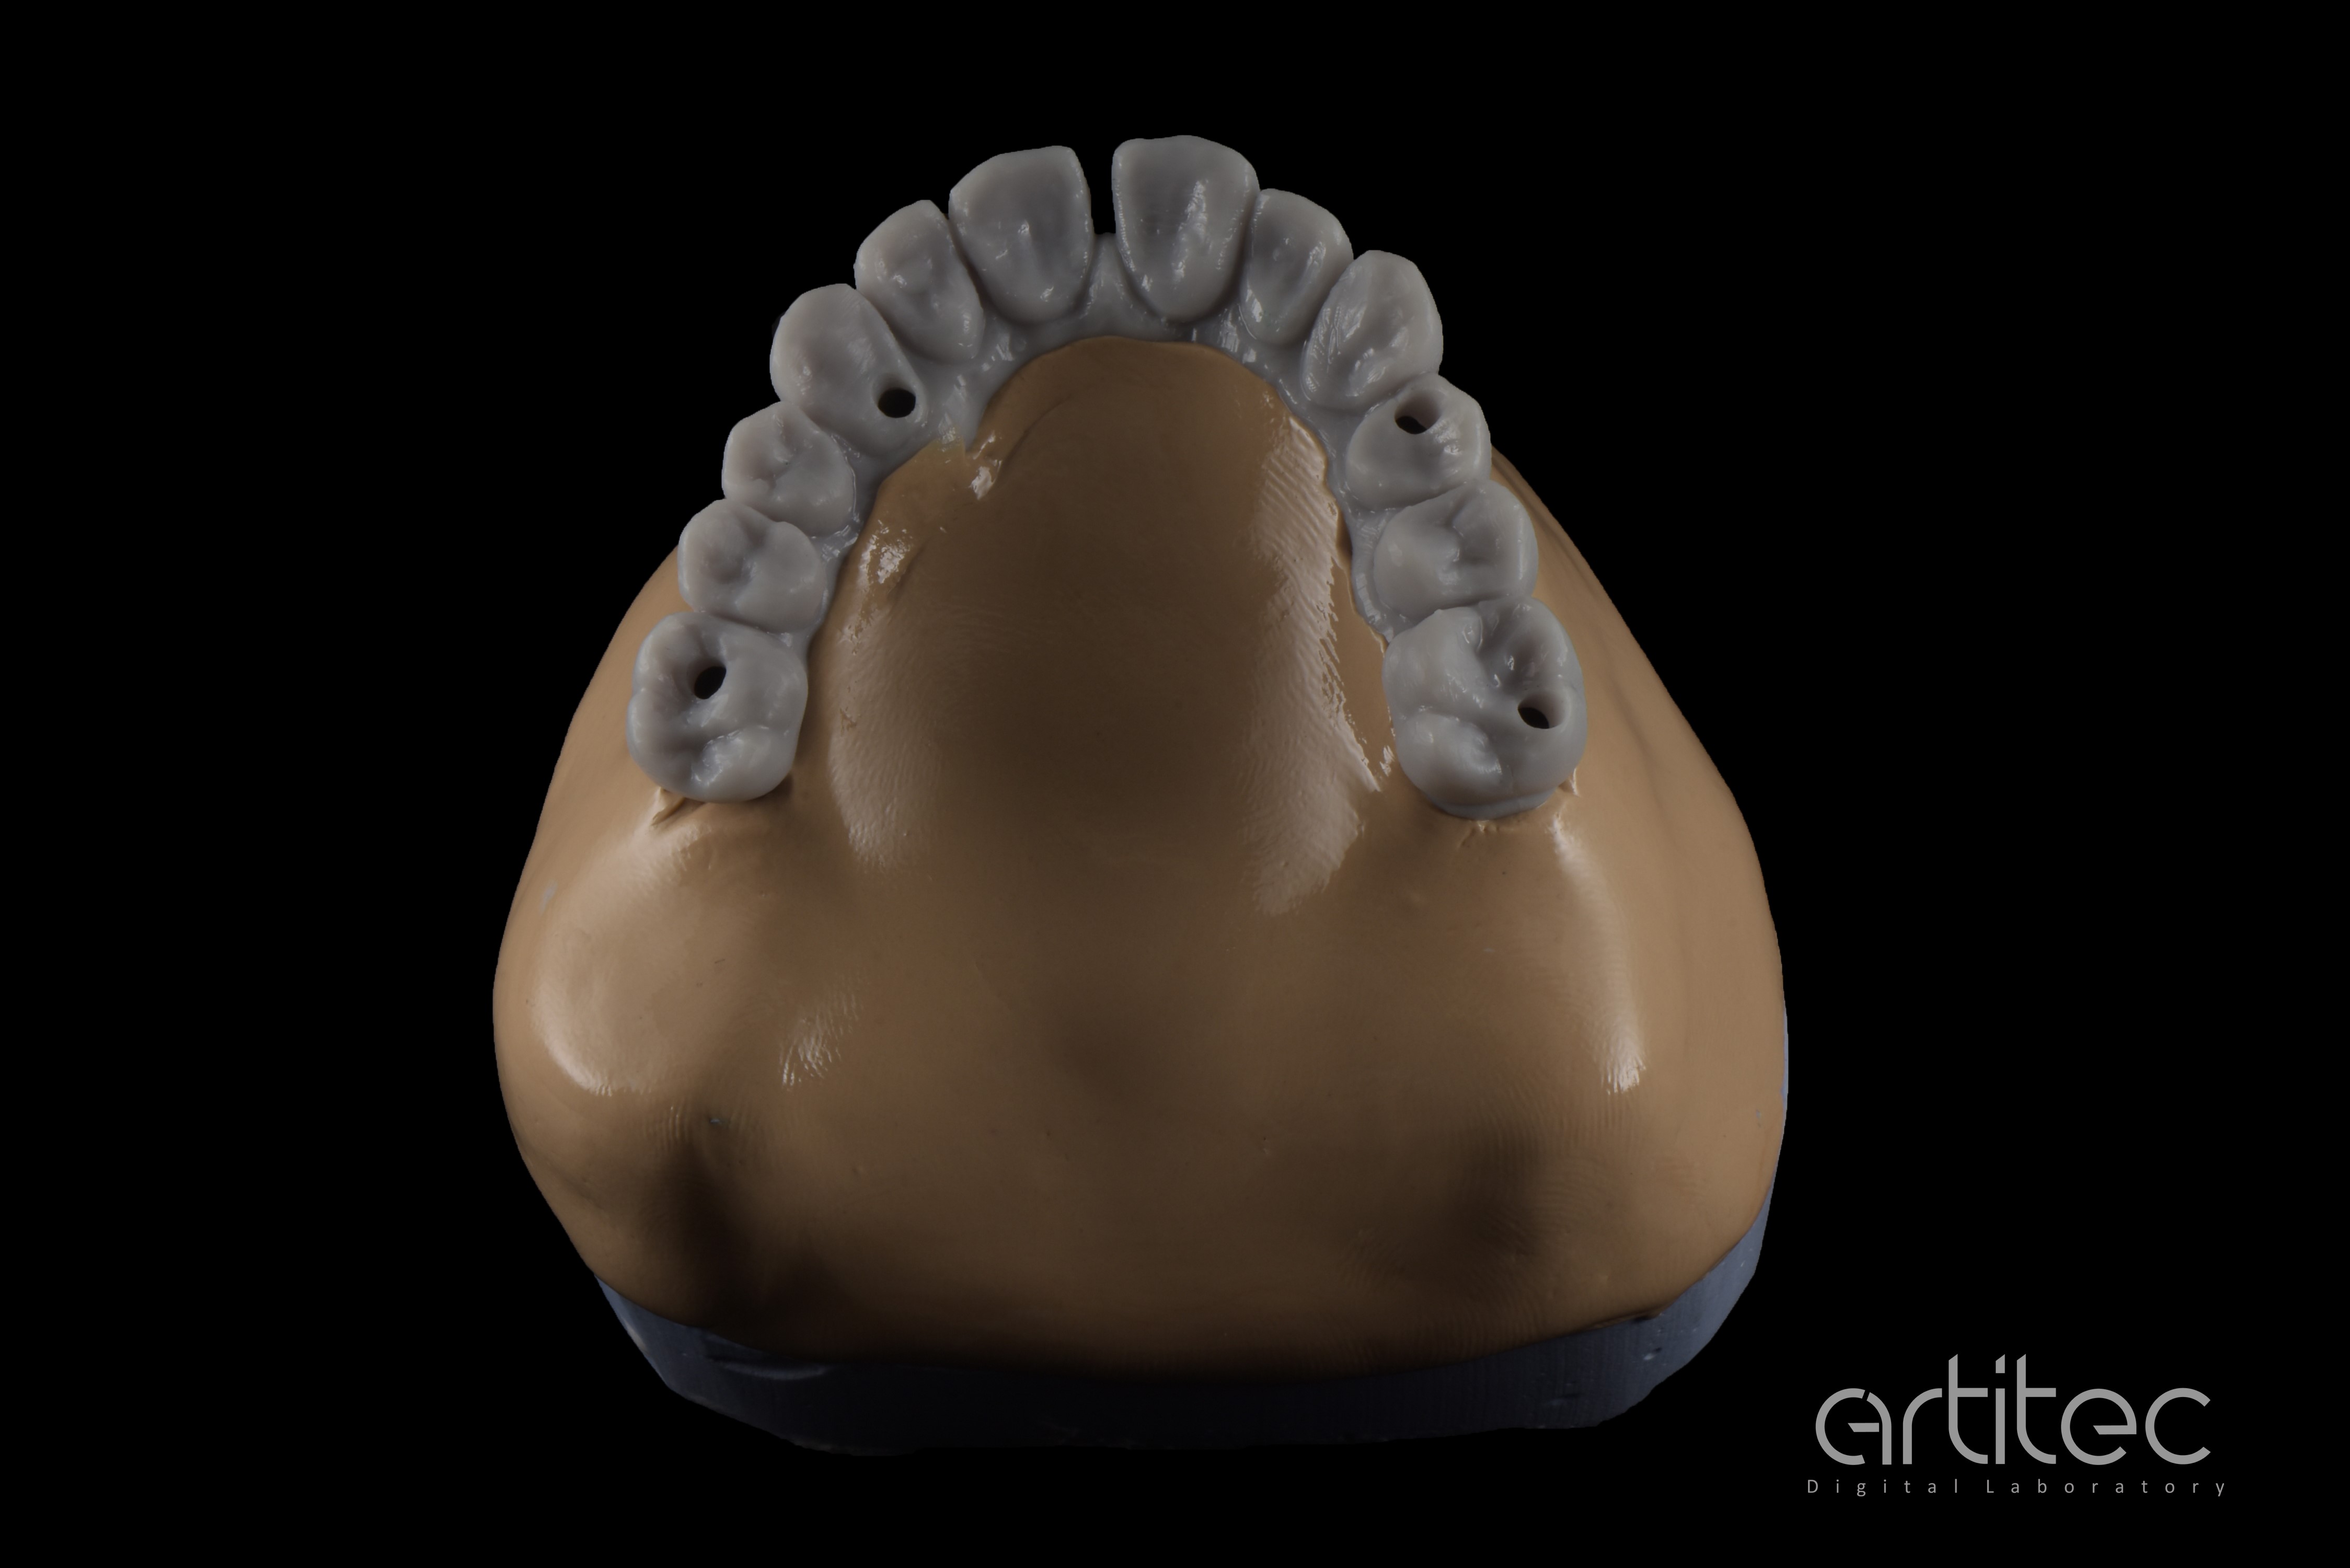

Fig. 1 Situazione iniziale del paziente con protesi di Toronto provvisoria

Fig. 18 Realizzazione del modello ibrido

Fig. 19 Provino da stampa 3D del progetto definitivo

Fig. 20 Vista occlusale del provino da stampa 3D del progetto definitivo